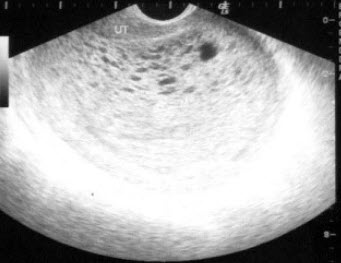

24、单项选择题 胰头的钩突部后方为下腔静脉,前方为()

女性,32岁,停经45天,B超检查如图,最可能的诊断为()

A.宫腔积液

B.宫体肌瘤

C.早期妊娠

D.子宫粘膜下肌瘤

E.卵巢囊肿